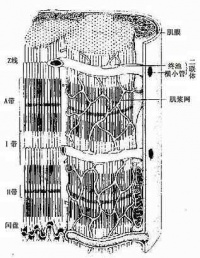

心肌细胞与骨骼肌的结构基本相似,也有横纹,但在结构上具有以下几个特征:

②心肌细胞的细胞核多位于细胞中部,形状似椭圆或似长方形,其长轴与肌原纤维的方向一致。肌原纤维绕核而行,核的两端富有肌浆,其中含有丰富的糖原颗粒和线粒体,以适应心肌持续性节律收缩活动的需要。从横断面来看,心肌细胞的直径比骨骼肌小,前者约为15微米,而后者则为100微米左右。从纵断面来看,心肌细胞的肌节长度也比骨骼肌的肌节为短。

③在电子显微镜下观察,也可看到心肌细胞的肌原纤维、横小管、肌质网、线粒体、糖原、脂肪等超微结构。但是心肌细胞与骨骼肌有所不同;心肌细胞的肌原纤维粗细差别很大,介于0.2~2.3微米间;同时,粗的肌原纤维与细的肌原纤维可相互移行,相邻者又彼此接近以致分界不清。心肌细胞的横小管位于Z线水平,多种哺乳动物均有纵轴向伸出,管径约0.2微米。而骨骼肌的横小管位于A-I带交界处,无纵轴向伸出,管径较大,约0.4微米。心肌细胞的肌质网丛状居中间,侧终池不多,与横小管不广泛相贴。总之,心肌细胞与骨骼肌细胞在形态和功能上均各有其特点。